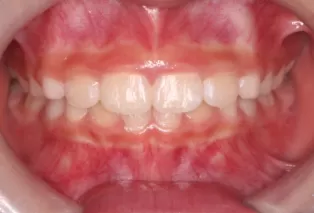

Intraoral photos